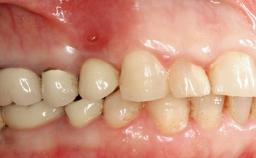

Removal of a Malpositioned Implant and Direct New Implant Placement with Simultaneous Contour Augmentation using GBR

A 35-year old female patient was referred to the Department of Oral Surgery and Stomatology at the University of Bern, Switzerland, for examination of an implant site that had exhibited clinical signs of slightly delayed wound healing. In addition, the referring clinician found no evidence for a facial bone wall when she raised a flap to gain access to the implant for abutment connection. Four months earlier, she had inserted a bone-level implant in a single-tooth gap, where the lateral incisor had been extracted due to a chronic periapical lesion on the mesial aspect of the root. Implant placement was combined with simultaneous bone augmentation using deproteinized bovine bone mineral (DBBM, Bio-Oss®; Geistlich, Wolhusen, Switzerland) and a collagen membrane (Bio- Gide®; Geistlich), followed by primary wound closure. The patient also provided the postsurgical radiograph that displayed the implant with a 3.5-mm healing cap.